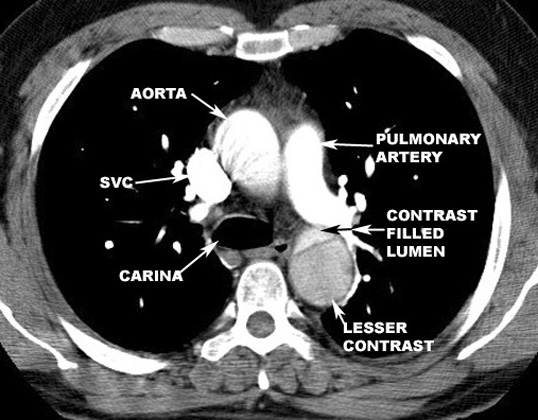

Aortic Dissection CT

Dissection Aorta CT

• Arrowheads: Intimal flap

Radiologic Criteria for Dissection in CT scanning:

• The diagnosis of aortic dissection by CT requires the identification of two distinct lumens with a visible intimal flap:

• False lumen

• Flap

• True lumen

• Indirect signs include compression of the true lumen by the false lumen, spiraling of a thrombosed false lumen, displaced intimal calcification, widening of the aortic lumen, and ulcer-like projections of contrast material.

• The advantages of CT include ready availability and the fact that it is a noninvasive procedure.

• It is also helpful in identifying causes of aortic widening other than dissection (such as tumors or periaortic hematomas), and can identify the presence of a pericardial effusion.

• It is disadvantageous in that it cannot identify the presence of aortic insufficiency or delineate coronary arteries.

• Contrast-enhancing CT scanning has a reported sensitivity of 94%, but a specificity of only 87%.

• Current CT scanning techniques improve the accuracy of CT scanning in diagnosing aortic dissection.

• 3D reconstructed images provide remarkable details.